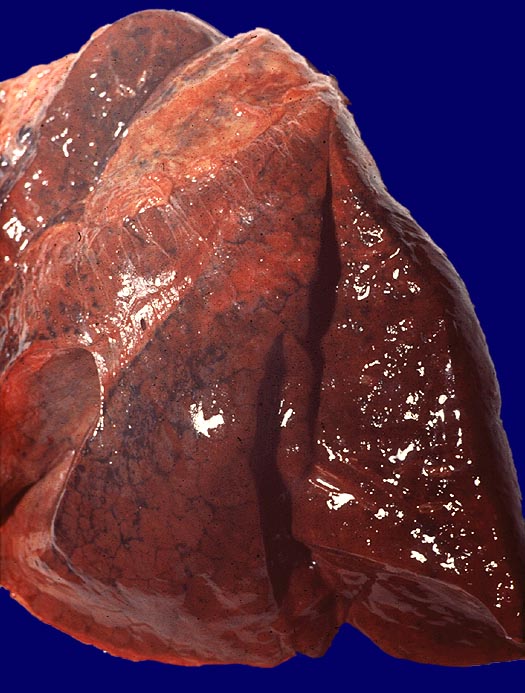

PathoPic – image database / PathoPic ID 2816 - Konfluierte hämorrhagische Grippe Pneumonie

Konfluierte hämorrhagische Grippe Pneumonie

Der ganze Lungelappen ist rot blau verfärbt und hämorrhagisch. Die Pleuraoberfläche zeigt Verwachsungsstränge. Eine fibrinöse Pleuritis liegt nicht vor.

Grippe-Epidemie 1957